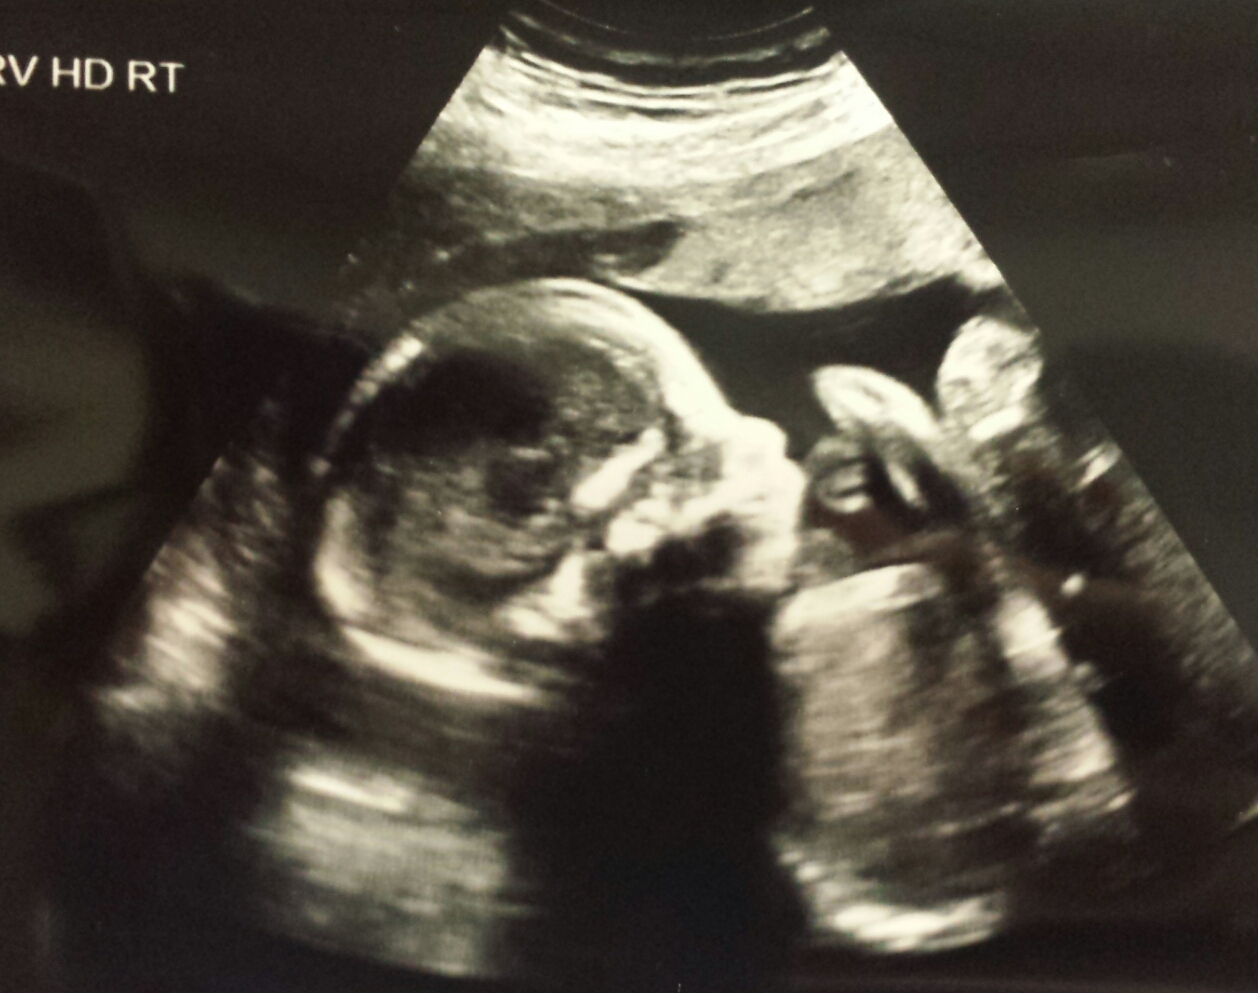

Team yellow, but would love to hear your thoughts based on skull theory, or just a feeling when seeing my babe! Attachment 25170Attachment 25171Attachment 251729

My guess on skull is girl because it has a tiny chin like my little girl did. But that is really not a reliable method UNLESS you compare to your boys' shots - the difference between my boys and my girl seemed really obvious. Same exact shape of face and head, but smaller (even tho she weighed a lot)

Not great at head guesses but thinking girl. Didn't look the same as my DS's head shape.